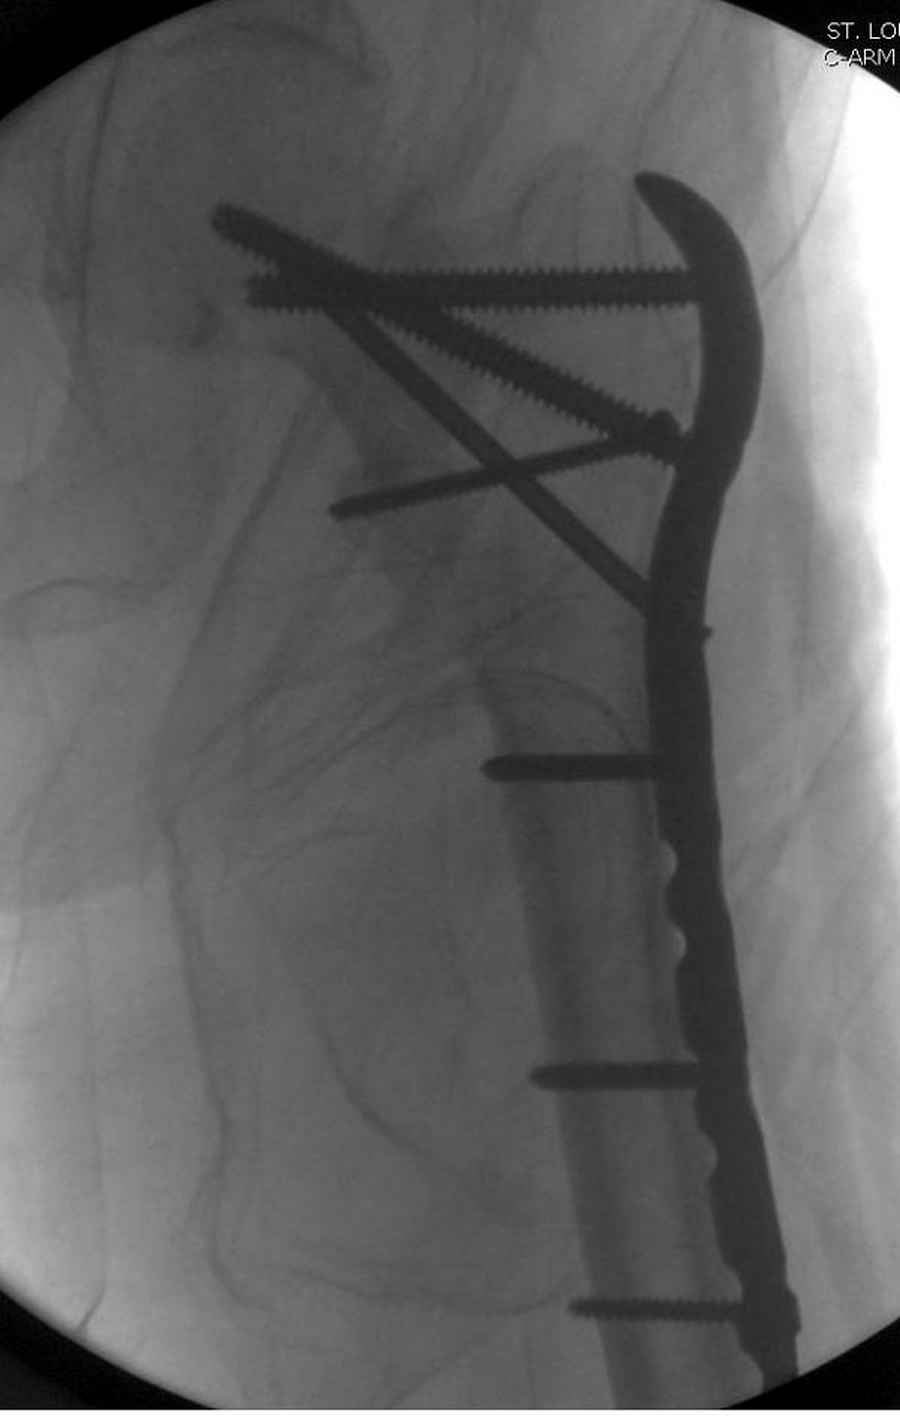

Из фиксаторов, мы бы применили цефаломедуллярные, потому что они "по закону моментов" из-за короткого рычага от центра головки к диафизу и по принципу "головка диафиз" механически лучше выдерживают нагрузки, чем пластины.

Но современные пластины с угловой стабильностью не отстают от медуллярных конструкций. Межфрагментарные шурупы и имплант как нейтрализирующее создаст адекватную фиксацию.

Здесь пара случаев фиксации похожих переломов:

первый высокоэнергетическая травма 36 лет